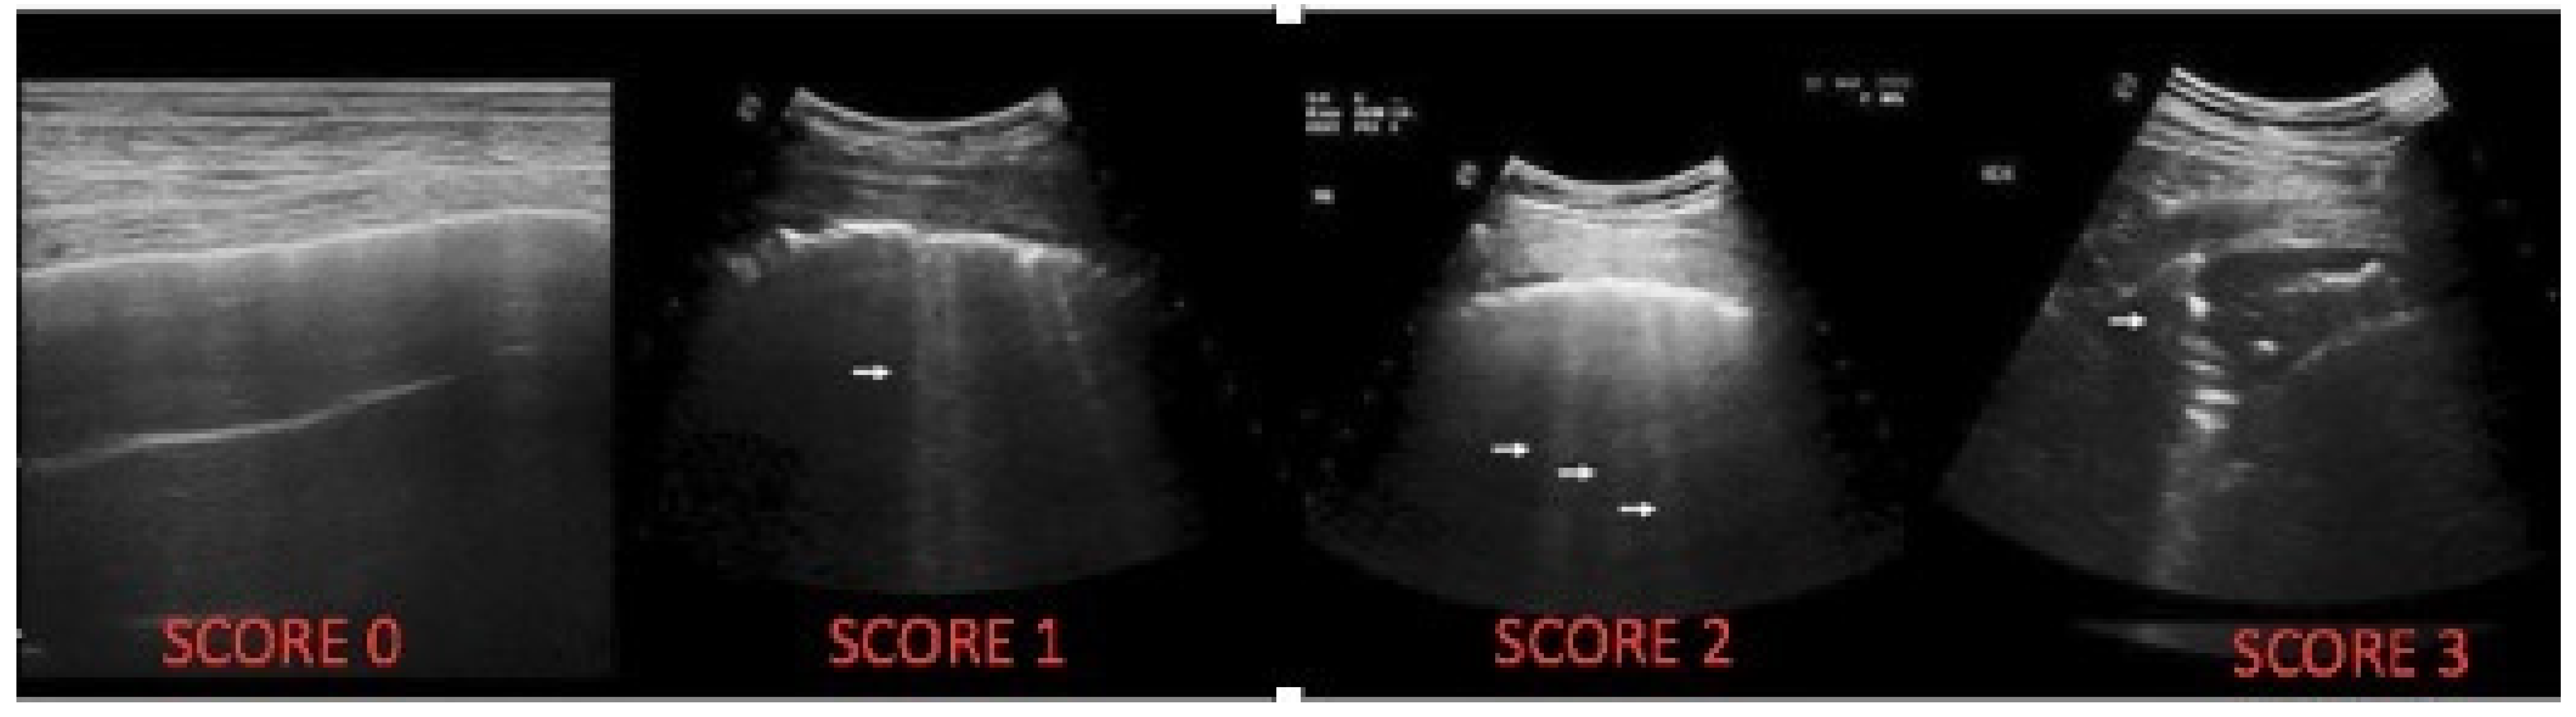

| LUS Artefact | Lung CF Score |

|---|---|

| Presence of A lines-normal aspect; distinctive B-lines < 3/ic space | 0 |

| Distinctive B-lines > 3/space or 1 coalescent B-line | 1 |

| Coalescent B-lines > 2/ic space | 2 |

| Consolidation < 1 cm | 3 |

| Consolidation > 1 cm, with bronchogram | 4 |

| Atelectasis/consolidation without bronchogram, >1 cm | 5 |